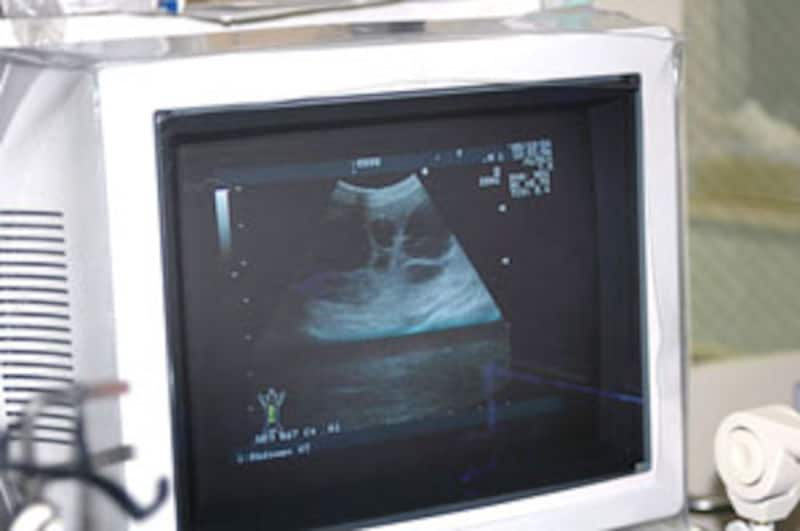

赤坂動物病院医療ディレクター石田先生による、内臓のエコー検査です。

ワカバちゃんの嚢胞はしっかり画面に映し出されました。

まるで教科書に登場するかのようにはっきりと黒い水のかたまりが何個も見えました。

ワカバちゃんの腎臓は4~50%機能しているのではないか?という診断です。